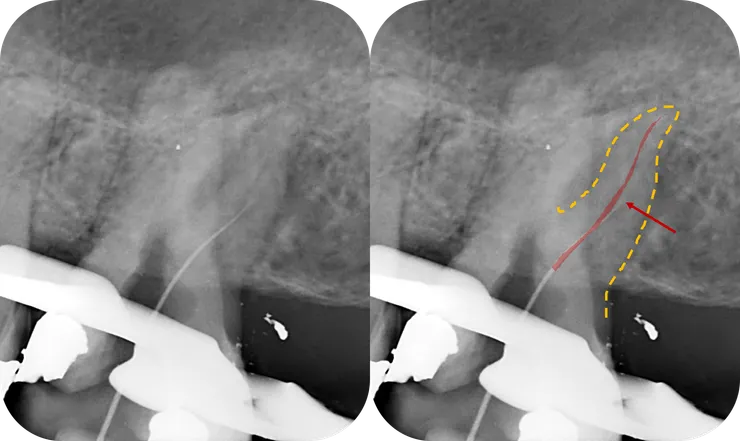

如同開場白強調的,任何 case 在開始前,務必、千萬、一定要先看清楚 root form (橘色虛線) & canal path (紅線)!

就算 canal 鈣化到看不到,也可以依據 root form 來推測出 canal 可能的走向。

如右圖所示,從依據 root form 推測出的 canal path 看來,原本的路徑似乎偏移不大,是不是繼續往下鑽就可以了呢?

果然,從 CBCT 才能看清真相!

(因為 B & D canal 的關鍵點太深了拍不到,因此本篇只 focus 在 ML canal.)

不光是 PA film, 在 CBCT 上我們也可以依據 root form 推測出 canal 的走向 (如下排圖中的紅色標示處)。於是我們可以清楚地看出,先前的路徑 (粉紅色箭頭標示處) 明顯地往 lingual & mesial 偏移,並勘勘在 perforation 前停住......

所以真正的路徑應該會是在舊充填的 DB side.

可以發現,前一位醫師的路徑有些許偏移,然後在 canal 中段彎折處 (紅色箭頭所指處) 製造出 ledge 而因此卡住......

結果發現到達的深度跟前一位醫師一模模一樣樣...... (比較圖 1 & 4)

然而不同的是,經過 coronal enlarge 後,此時 file 的自由度變大了 (注意到紅色箭頭所指的 orifice 附近的彎度變直了),file tip 的手感就變清晰了!

再搭配圖 2 得知路徑應往 mesial 修正,搭配圖 3 得知 canal 中段以下往 buccal 彎,於是我在 file tip 1mm 處彎了一個小小彎,往 M/B 方向找 --->